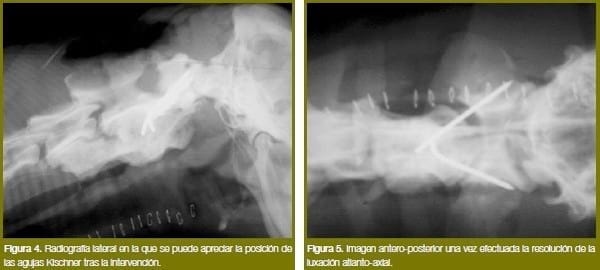

Después de reducir la luxación y comprobar la correcta posición anatómica de las vértebras realizamos un cuidadoso legrado del cartílago articular en esta zona. A continuación se insertan unas agujas de Kischner de 2 mm de diámetro de ventral a dorsal y con una angulación de medial a lateral, que permitan su inserción en el cuerpo vertebral del axis para traspasar las corticales del ala del atlas.

Posteriormente, se corta el extremo visible de las agujas de Kischner y se procede a su doblado en forma de mango de paraguas (figuras 4 y 5).